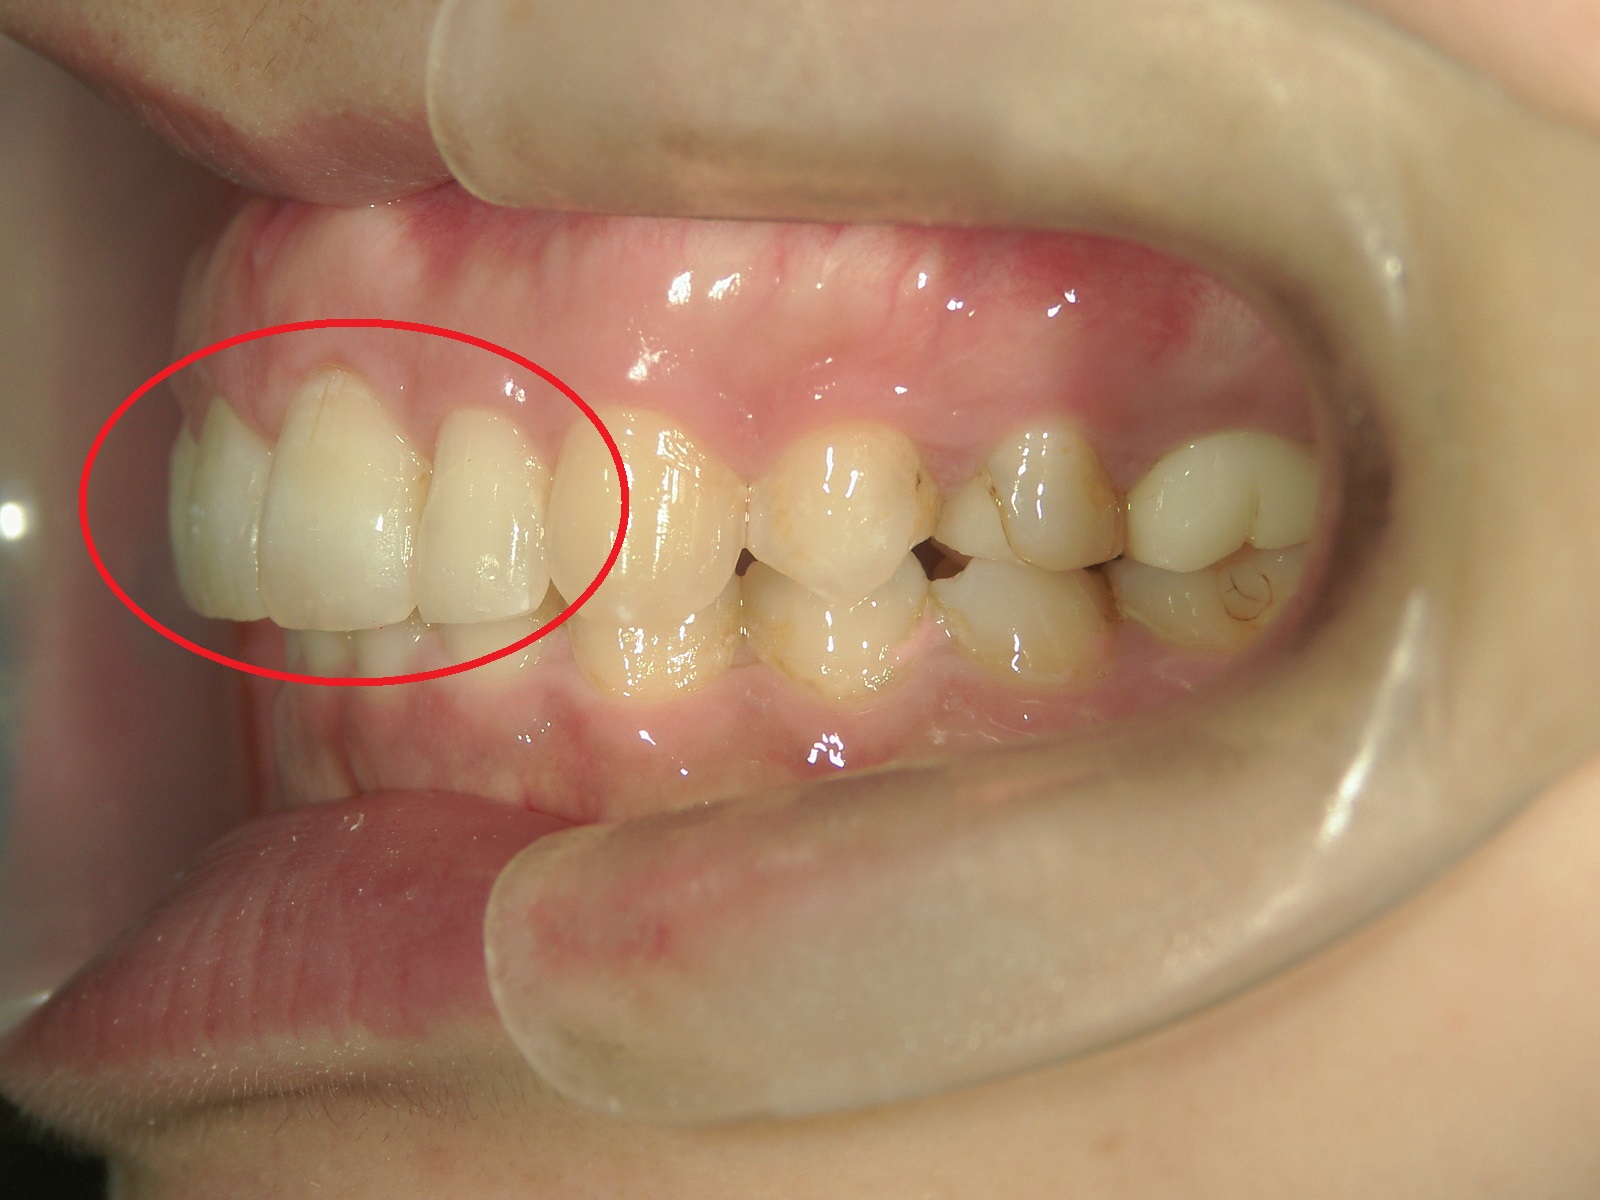

ワンポイント矯正 症例(4)

主訴: 左上前歯が前に出ていて気になる。